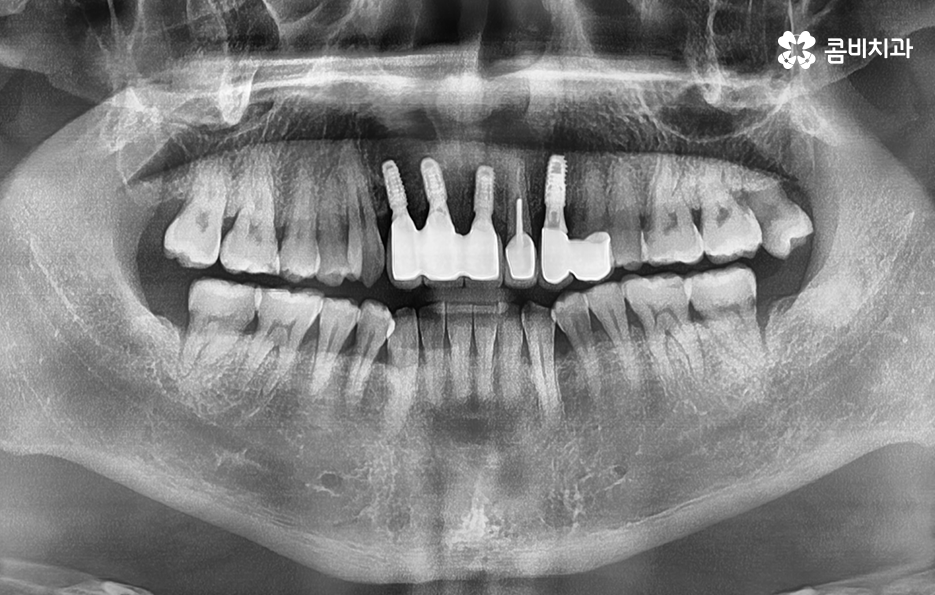

이렇게 앞니가 상실되면 심미적, 기능적 불편이 크기 때문에 많은 분들이 앞이빨 임플란트 과정을 거치게 되는데 앞니 임플란트는 어금니와는 다른 부분에서 좀더 정교한 치료가 필요하며 앞니 부위는 뼈가 얇고 심미성이 중요한 부위라는 점에서 잇몸 라인, 앞니의 각도, 심미성, 주변 치아와의 조화까지 모두 맞아야 자연스럽게 보이므로 정교한 치료의 중요성이 더 높은 부위라고 할 수 있어요

그리고 앞니는 씹는 힘이 약해 보이지만 가로 방향 힘이 많이 가해져서 임플란트에 부담을 주기 쉽고 앞니 상실의 원인이 치주염이라면 뼈가 많이 녹아 있는 경우가 많아 뼈 이식이 필수적인 상황이 자주 생기므로 앞이빨 임플란트 과정에서 주의해야 할 점들에 대해 잘 알고 접근하는 것이 중요한 거예요

또한 앞니는 잇몸의 모양이 심미성에 큰 영향을 주는데, 잇몸이 얇으면 임플란트가 비쳐 보이거나 잇몸 라인이 붕괴될 위험이 있어서 이런 경우에는 잇몸 두께를 보강하는 잇몸 이식술이 필요할 수 있으며 앞이빨 임플란트 과정 뿐 아니라 치료 후에도 잇몸 관리는 앞니 임플란트의 수명, 심미적인 유지에 있어서 중요한 요소라고 볼 수 있었어요